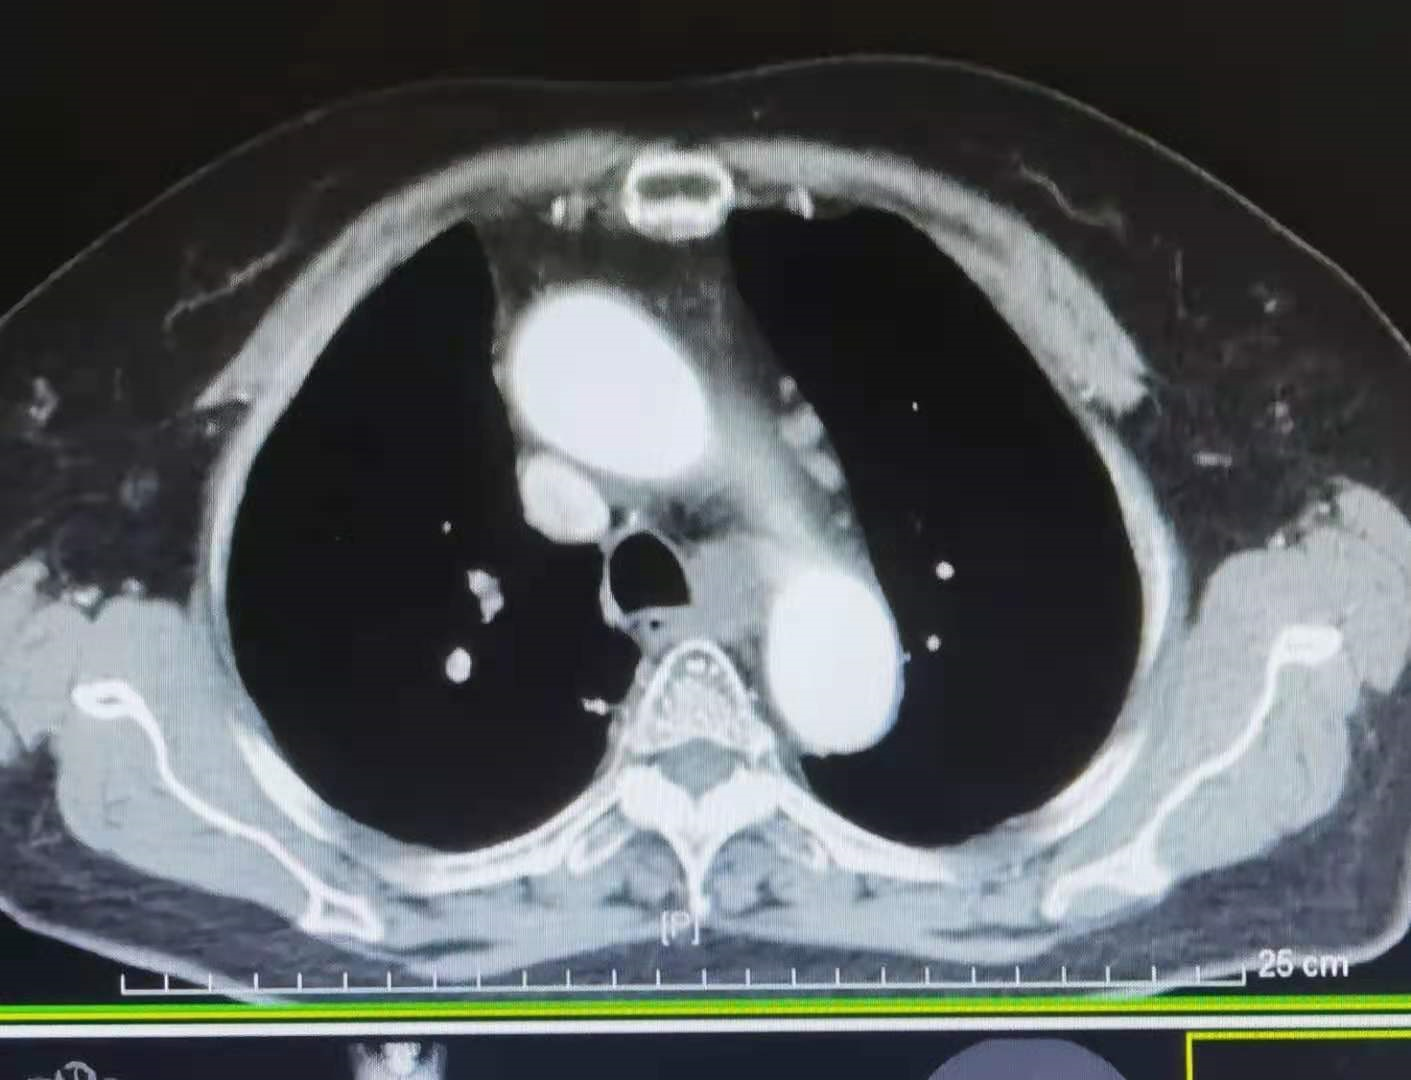

患者 , 孙某 , 女 , 66岁 , 患者2018年03月体检胸部CT:右肺下叶纵隔旁占位 , 约31mm*19mm 。 见图1、2、3 。 进一步行PET-CT检查 , 提示:右肺下叶后基底段大小约3cm*1.9cm的扁圆形软组织肿块 , FDG代谢异常增高 , 与胸膜宽基底相连 , 右胸廓入口、气管前腔静脉后、主动脉弓、右食管旁多发肿大淋巴结 , FDG代谢增高 , 考虑转移 。